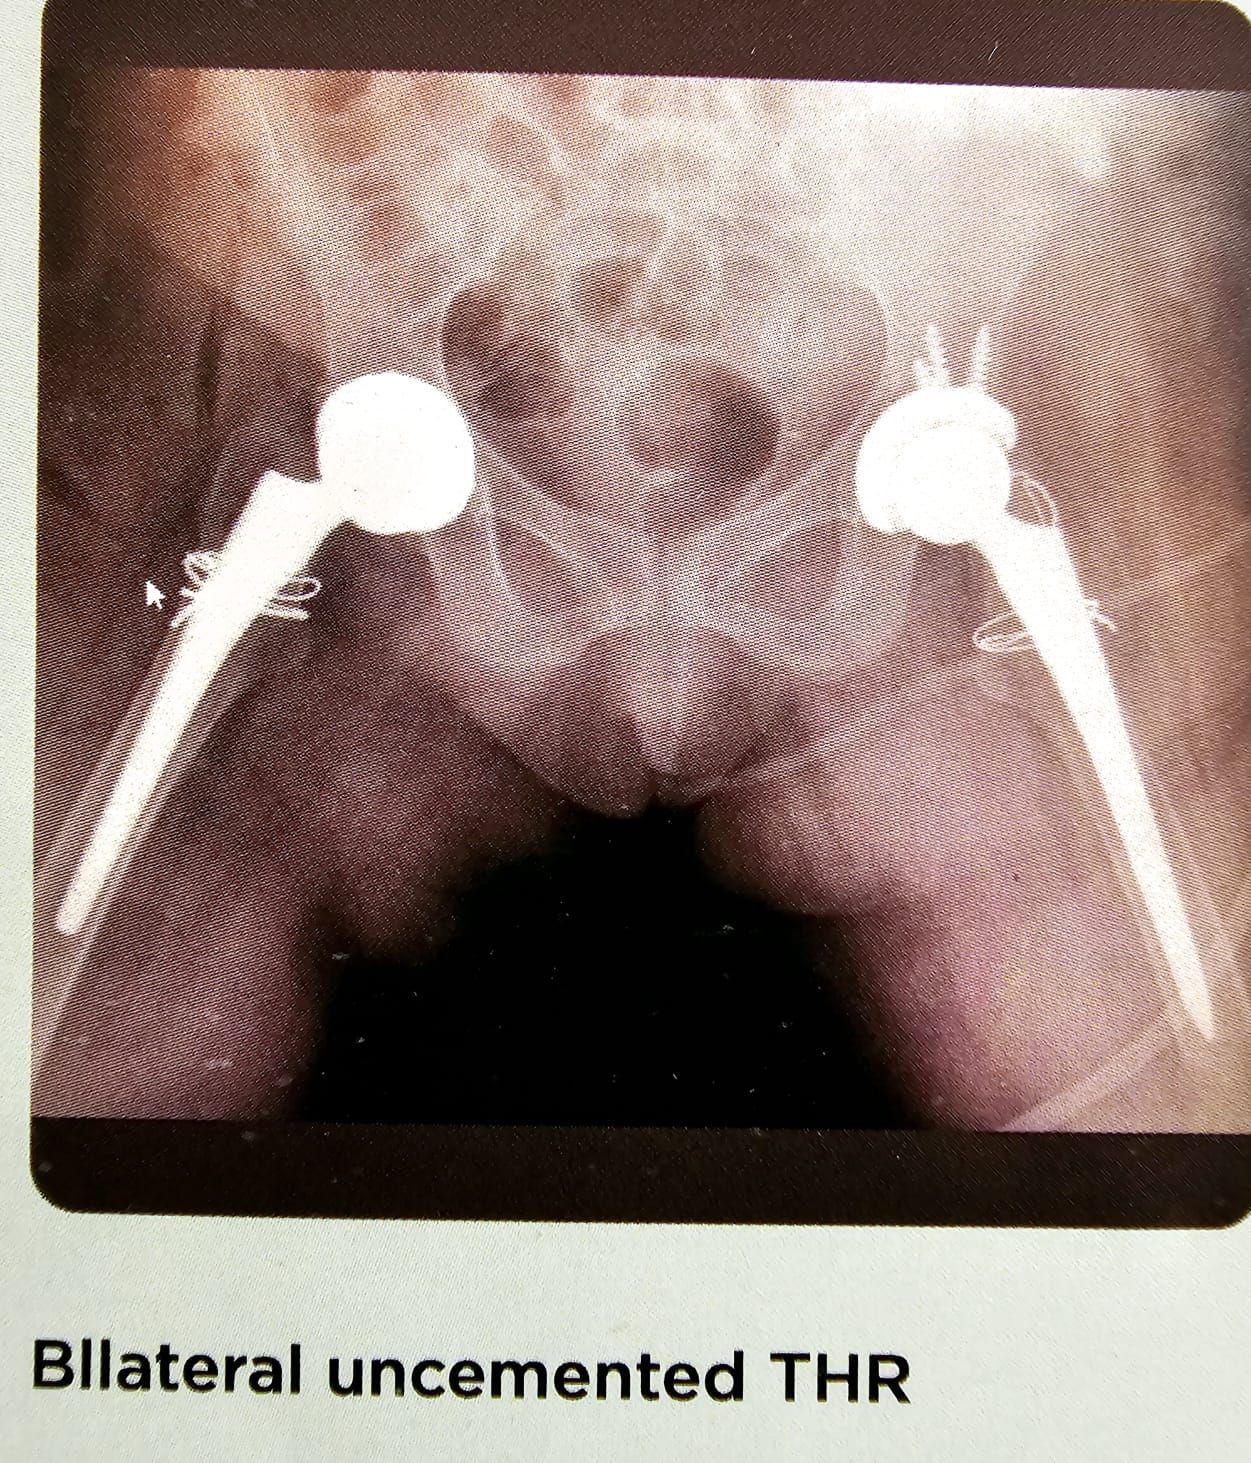

Bilateral uncemented THR

Another case of ABN with secondary OA in a young patient. Have done a bilateral un cemented total hip replacement in one sitting. Had to put screws on the left side, and profellatic circulage wires on both the stems, because of the un cemented femoral stems. Patient did very well and mobilized. Had full good range of motion. The case has been projected for the un cemented bilateral THR which has been done on single setting. See the 36MM head on both sides.